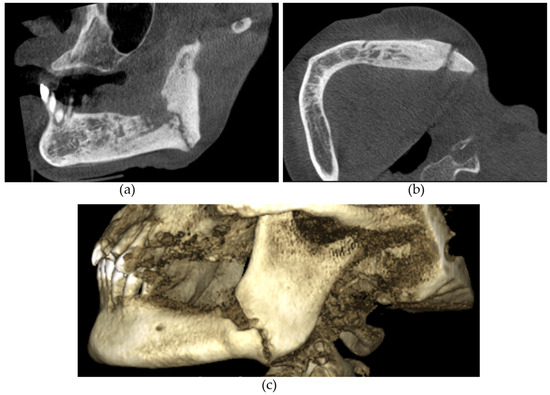

Figure 1. (a) Sagittal and (b) axial sections demonstrating an osteolytic lesion with sequestrations in the left mandible. Arrows demonstrate the sequestrations.